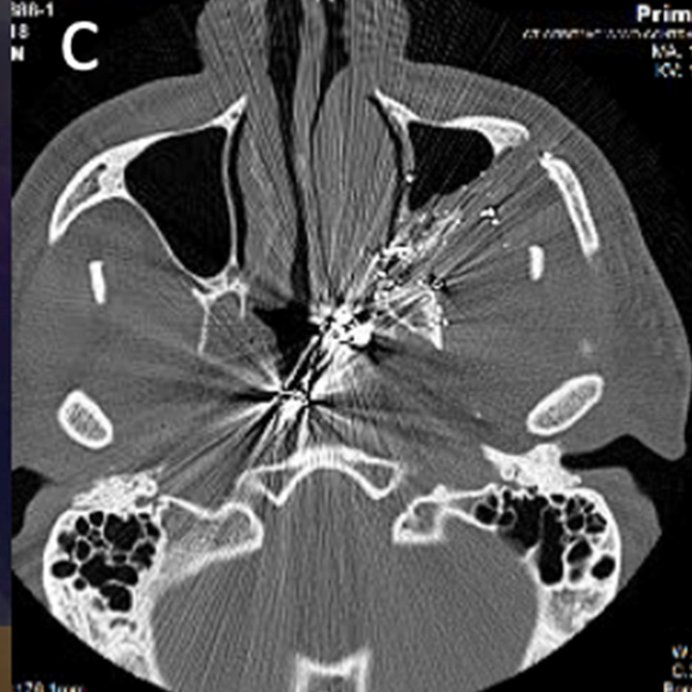

The correct answer for the poll below was actually "Eagle's Syndrome related trauma"! The patient had bilaterally elongated styloid processes seen in the image below, which along with calcified stylohyoid ligaments and the hyoid formed a ring in the neck sciencedirect.com/science/articl…

The ossification of these ligaments meant the loss of flexibility and, rather than accommodate the applied force, maintained their structure and pierced the retro-pharynx! Link to the case report is above!